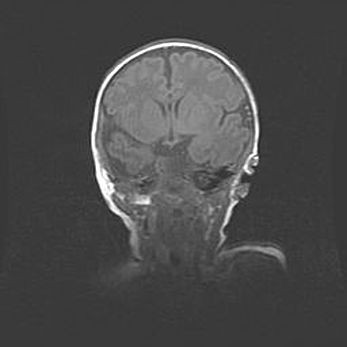

Церебральная ишемия II.

Возраст: 5 дней

Вес: 3400 г

Пол: женский

Окружность головы: 35 см

Срок гестации: 39 недель

Церебральная ишемия – это заболевание, характеризующееся недостаточностью (гипоксией) либо полным прекращением (аноксией) снабжения мозга кислородом по причине закупорки одного или нескольких сосудов. Это приводит к  что метаболическим расстройствам различной степени тяжести в тканях головного мозга, развитию коагуляционных некрозов и гибели нейронов.